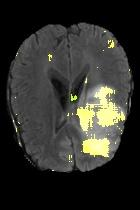

Current unsupervised anomaly localization approaches rely on generative models to learn the distribution of normal images, which is later used to identify potential anomalous regions derived from errors on the reconstructed images. However, a main limitation of nearly all prior literature is the need of employing anomalous images to set a class-specific threshold to locate the anomalies. This limits their usability in realistic scenarios, where only normal data is typically accessible. Despite this major drawback, only a handful of works have addressed this limitation, by integrating supervision on attention maps during training. In this work, we propose a novel formulation that does not require accessing images with abnormalities to define the threshold. Furthermore, and in contrast to very recent work, the proposed constraint is formulated in a more principled manner, leveraging well-known knowledge in constrained optimization. In particular, the equality constraint on the attention maps in prior work is replaced by an inequality constraint, which allows more flexibility. In addition, to address the limitations of penalty-based functions we employ an extension of the popular log-barrier methods to handle the constraint. Comprehensive experiments on the popular BRATS'19 dataset demonstrate that the proposed approach substantially outperforms relevant literature, establishing new state-of-the-art results for unsupervised lesion segmentation.